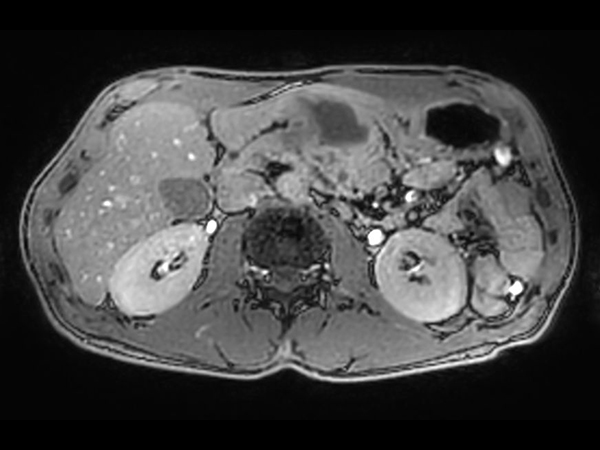

Axial T2w TSE MultiVane XD